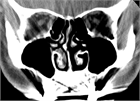

1. 鼻閉感は鼻閉塞に起因することが多いが、上咽頭疾患など鼻腔外の要因でも来し、さらに心身症や萎縮性鼻炎など、閉塞性の病変がなくても生じ得る。